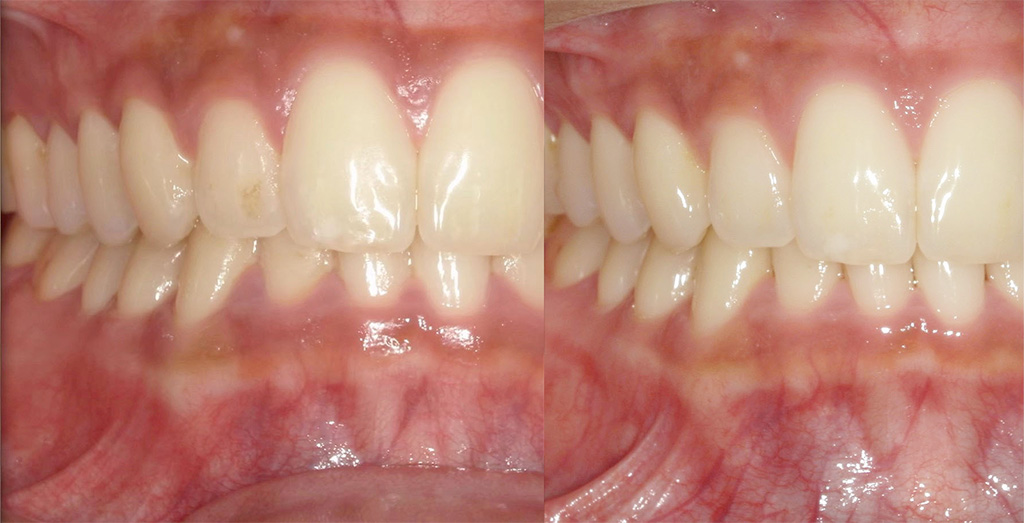

【2ヶ月後】ほぼ毎日フロスしたら…

2ヶ月後、ほぼ毎日フロスを続けた結果を比較してみたのがこちら。

● 歯ぐきの変化

● 清掃状態

● 本人の感想

「フロスするとき、40センチで全顎するのが難しい」

「奥歯が難しい」

「いっぱい取れた時たのしい」

「お肉食べた日すごい取れる」

とのことでした!